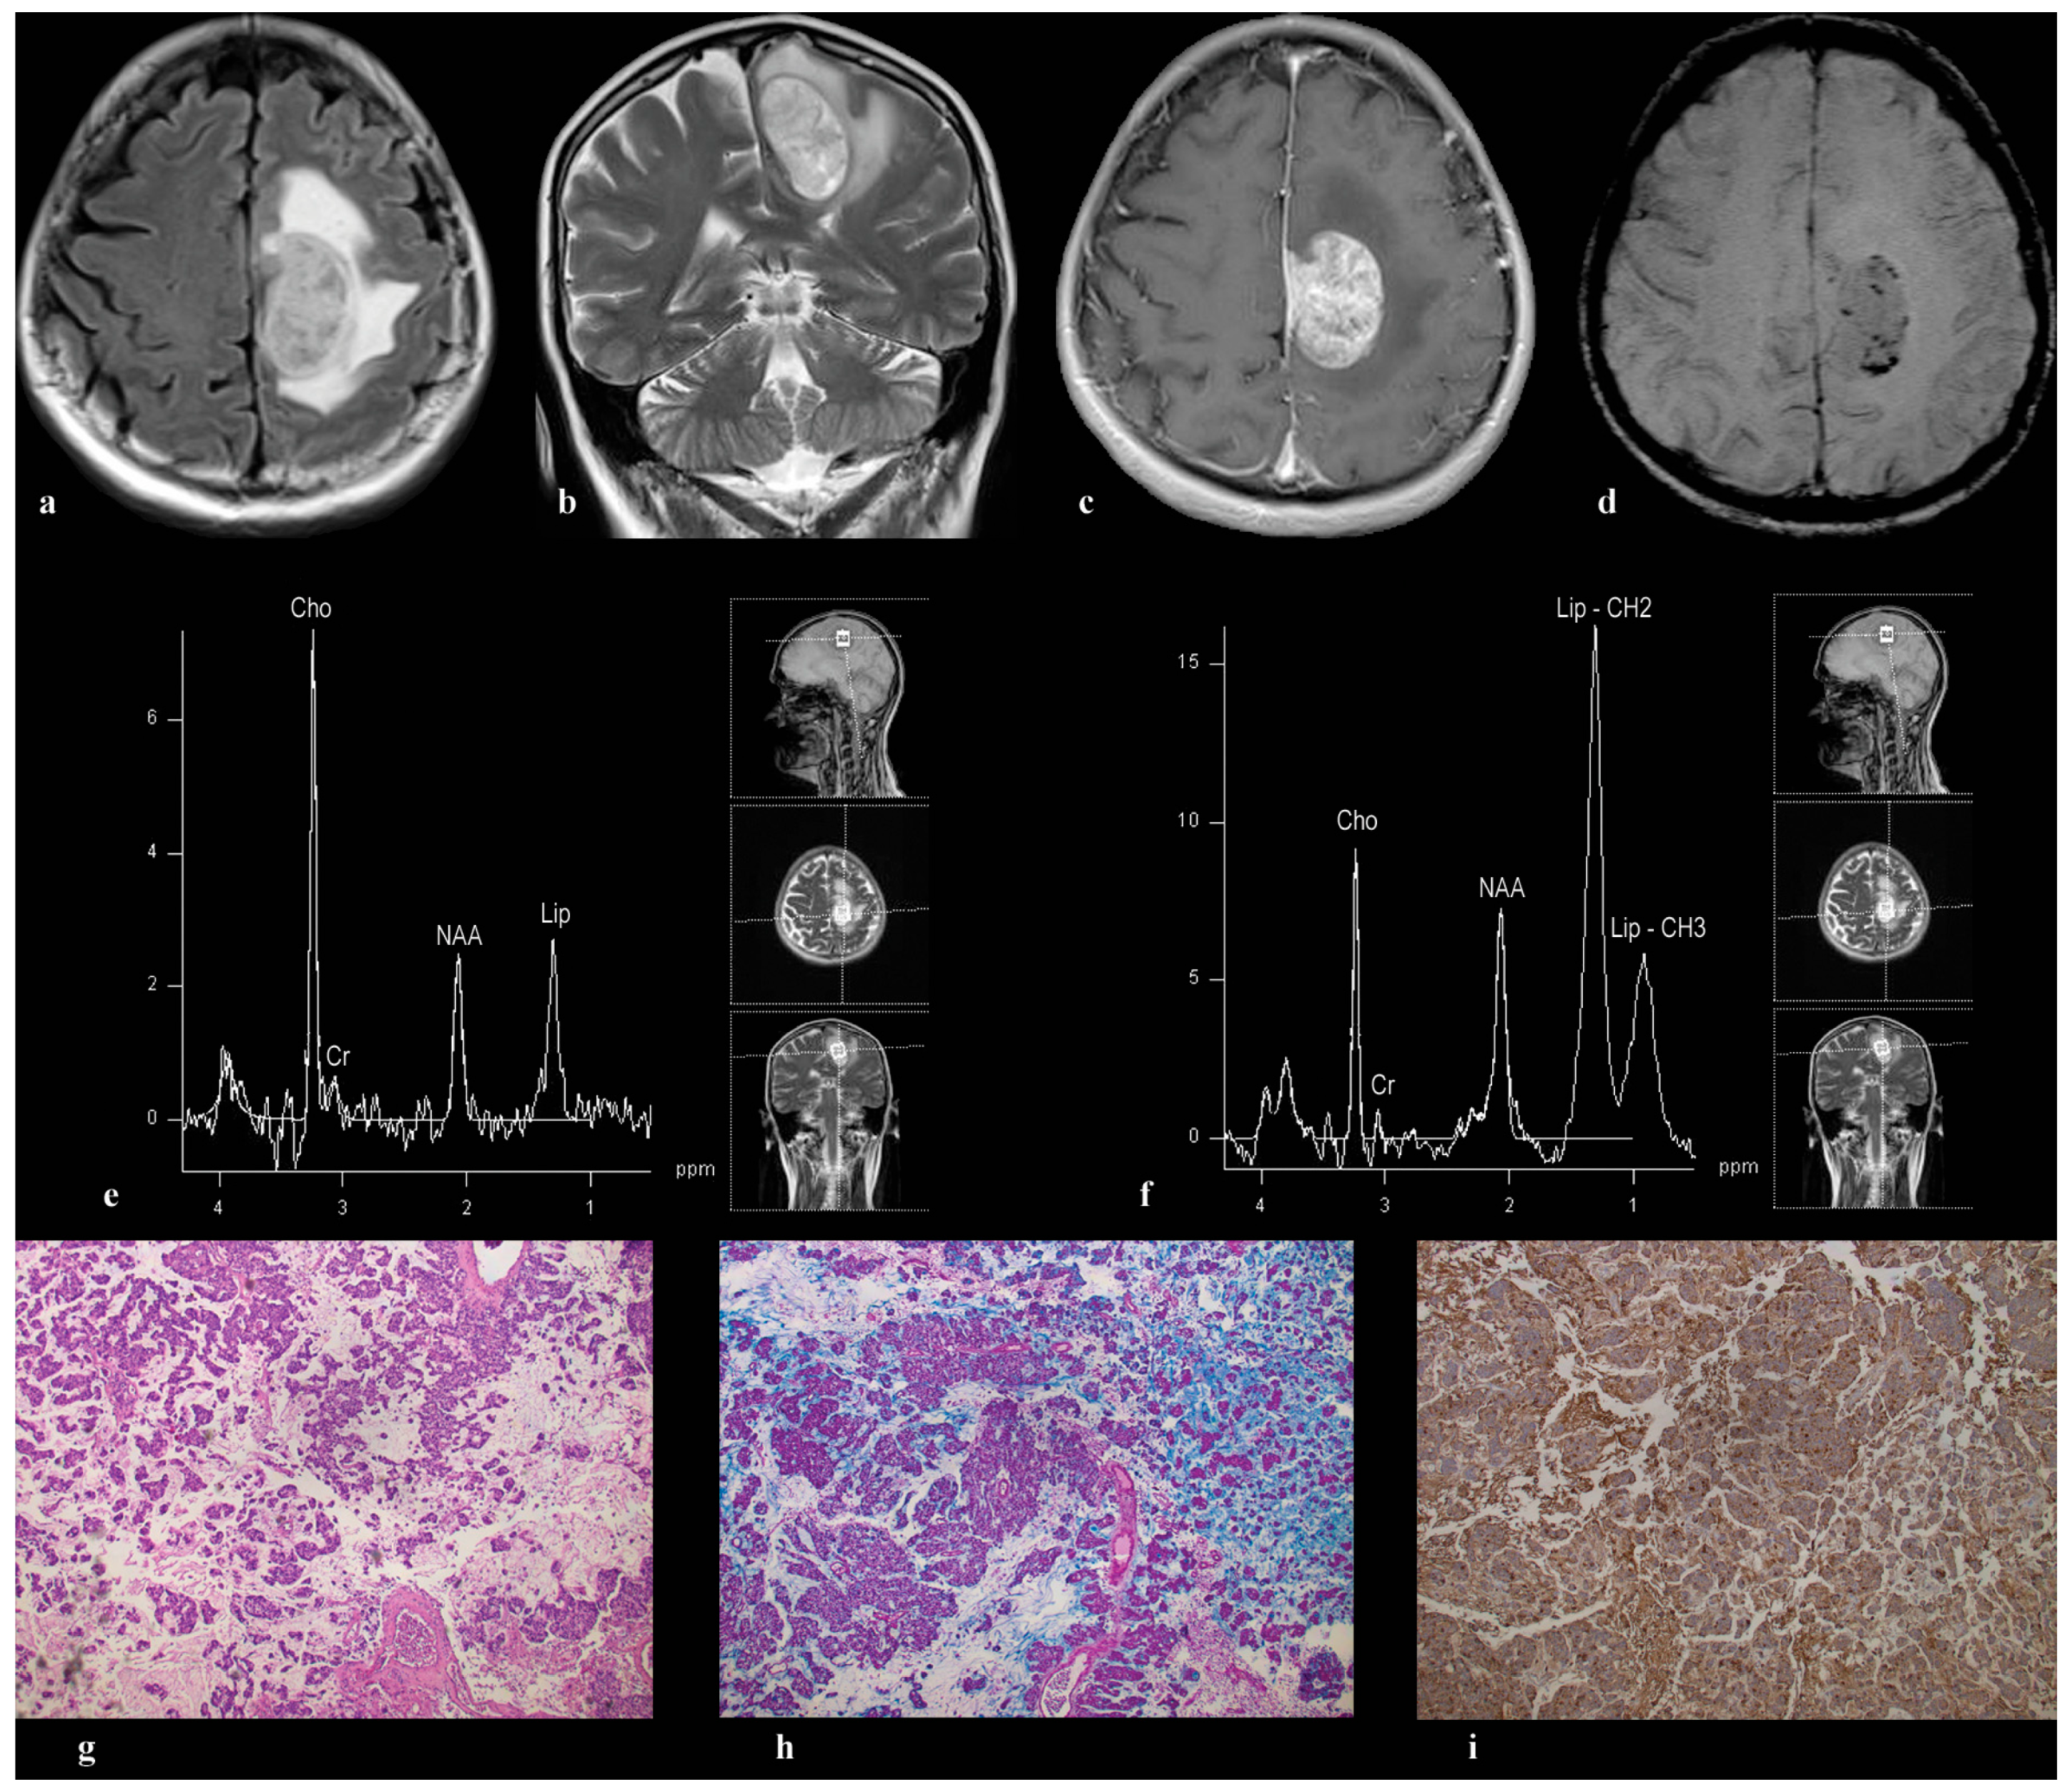

3.1. Patient 1

3.2. Patient 2